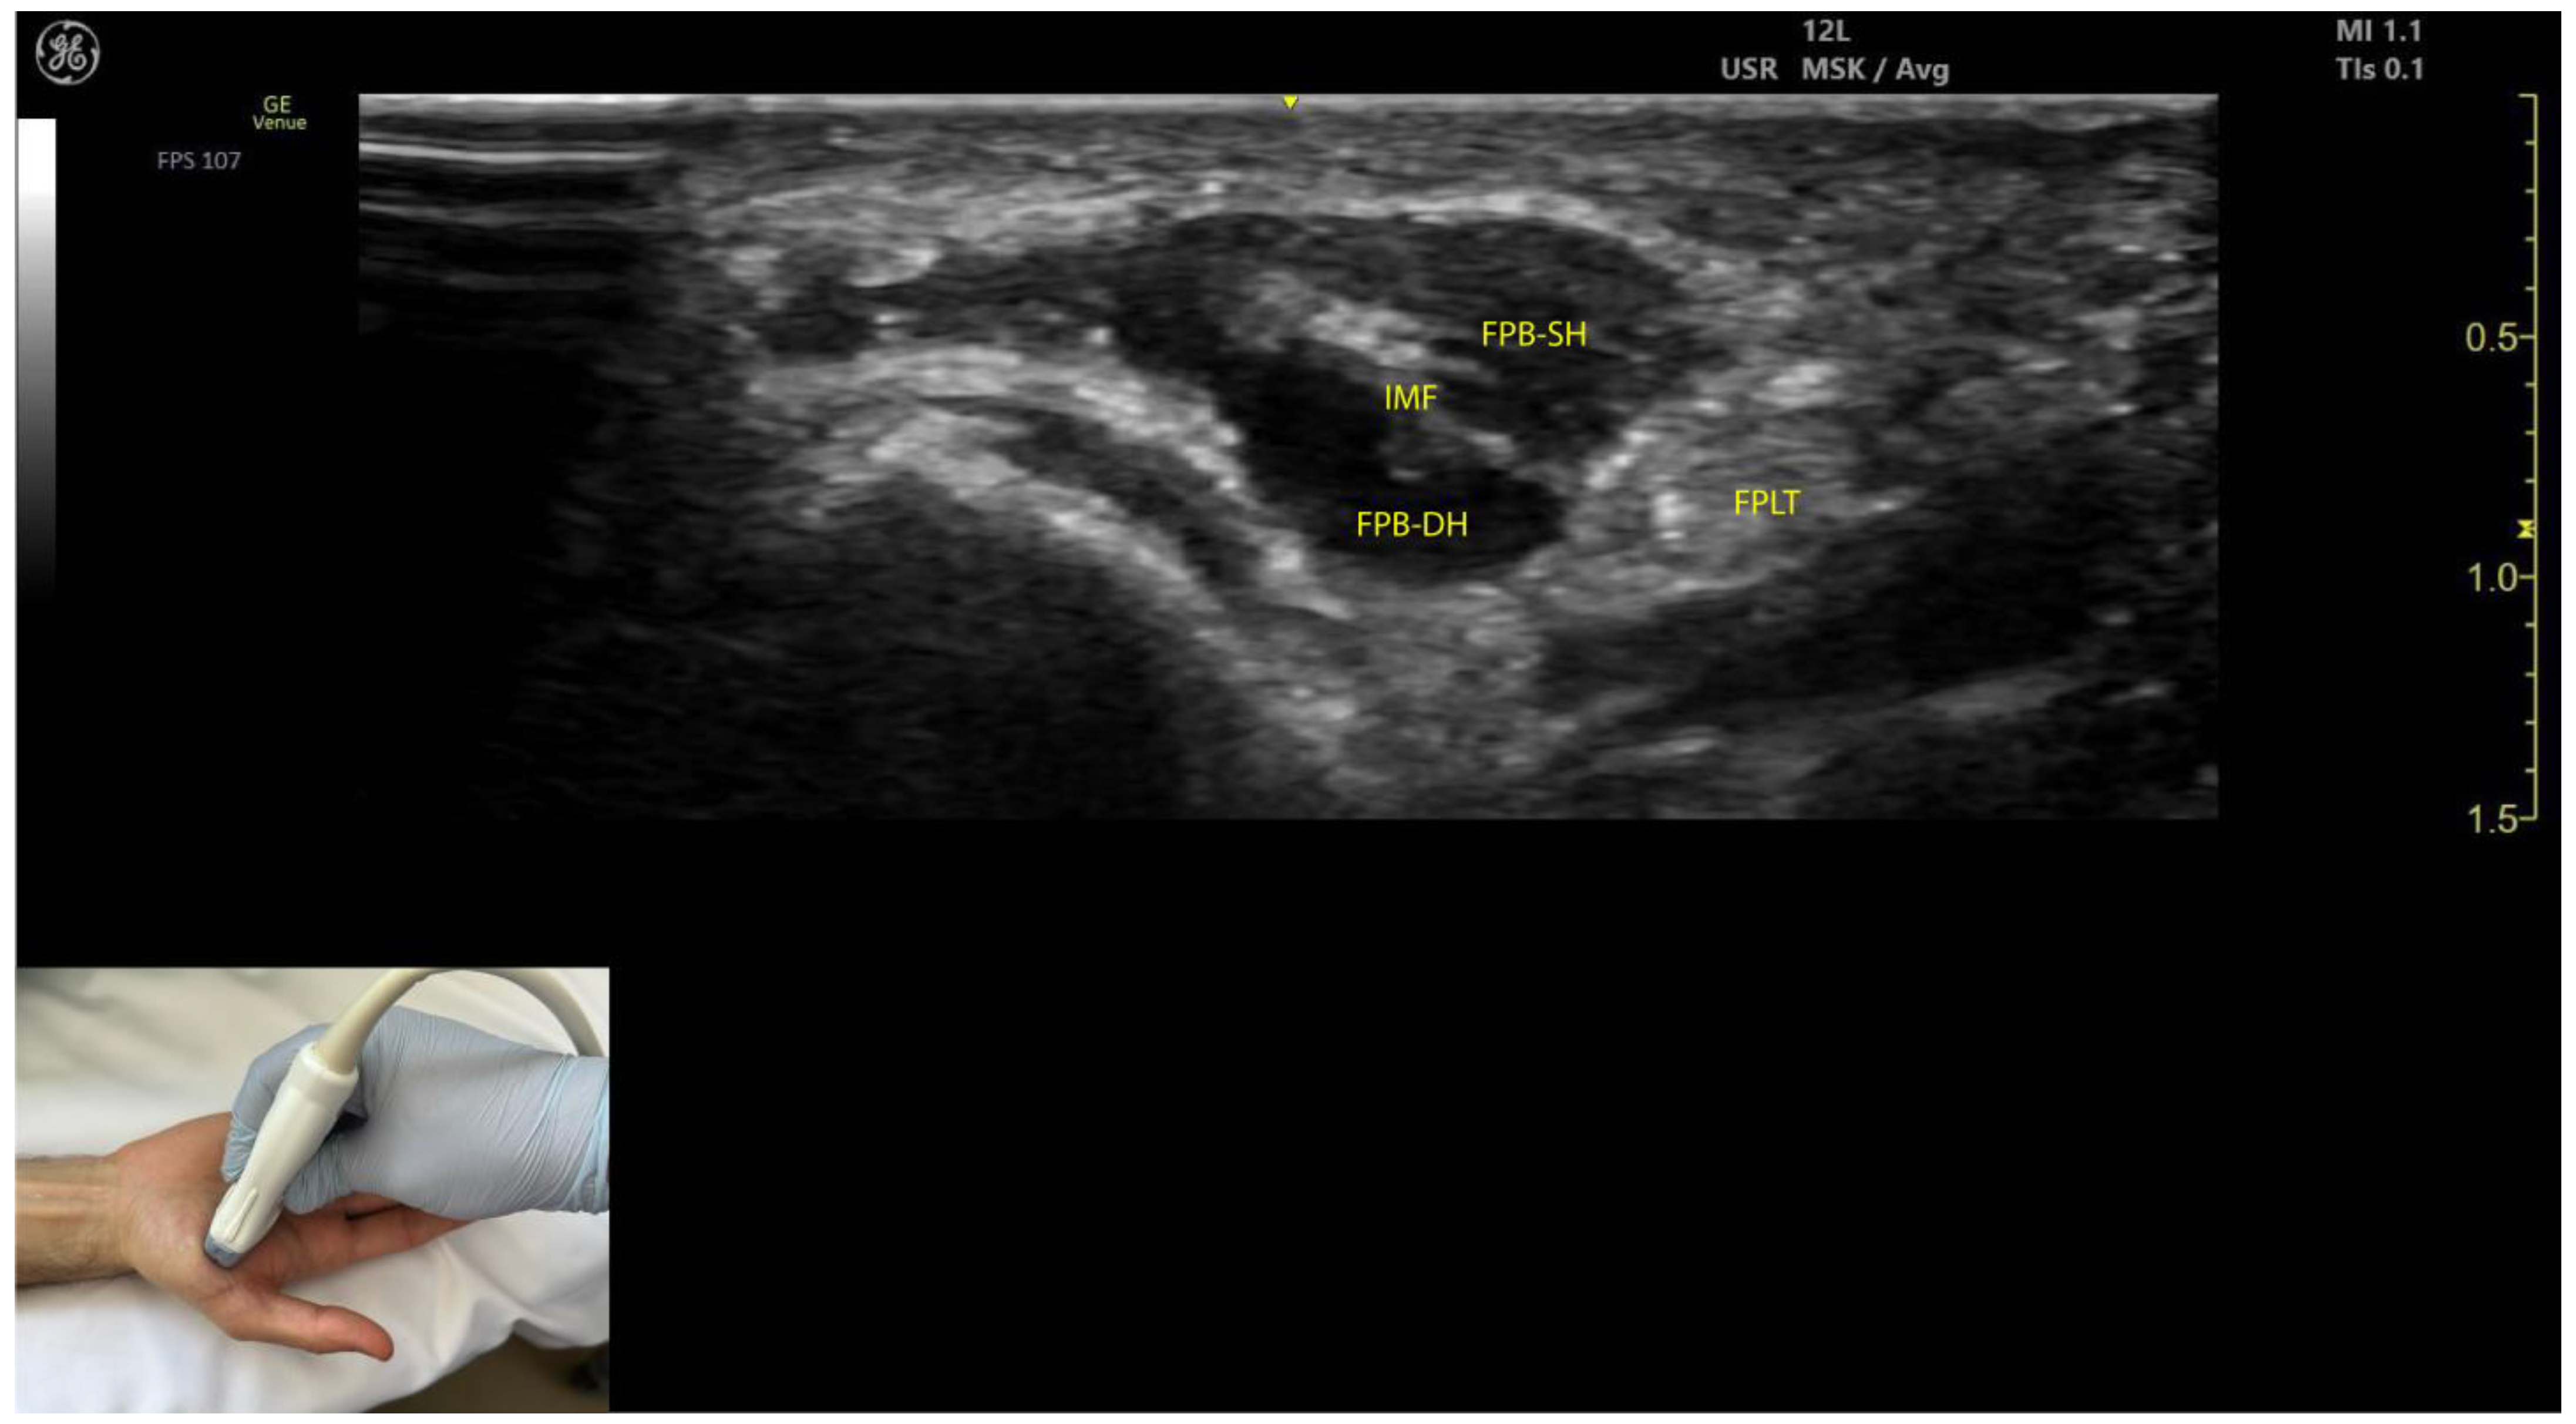

2.10.3. Key Ultrasound Landmarks (Figure 9)

- Muscle position: The FPB is the most medial muscle mass within the thenar eminence. It is situated medial to the APB and opponens pollicis and lateral to the adductor pollicis [56].

- Internal fascia: The FPB contains intramuscular fascia that separates its two heads—the superficial and deep heads—which can be targeted individually during injections [53];

- FPL tendon: Scanning toward the MCP joint reveals the FPL tendon located lateral to the superficial head of the FPB and deep to its deep head.

- External fascia: The FPB muscle lacks a pronounced fascia to clearly separate it from adjacent muscle masses, such as the abductor pollicis brevis and opponens pollicis, which may complicate precise localization during BoNT-A injections.

- Dynamic evaluation: Contraction of the FPB is observed during thumb flexion at the CMC and MCP joints [48].

2.10.4. Clinical Implications and Injection Strategy

- The region with the highest density of intramuscular nerve arborizations of the FPB is located 50–70% along the line connecting the hook of hamate to the head of the first metacarpal [51].

- In our clinical practice, the FPB is targeted for BoNT-A injections at the point of maximum muscle thickness, as determined by ultrasound. The optimal injection site is typically located at the midpoint of the thenar eminence. Ultrasound guidance ensures precise toxin delivery and allows for individual targeting of the superficial and deep heads, minimizing the risk of complications.